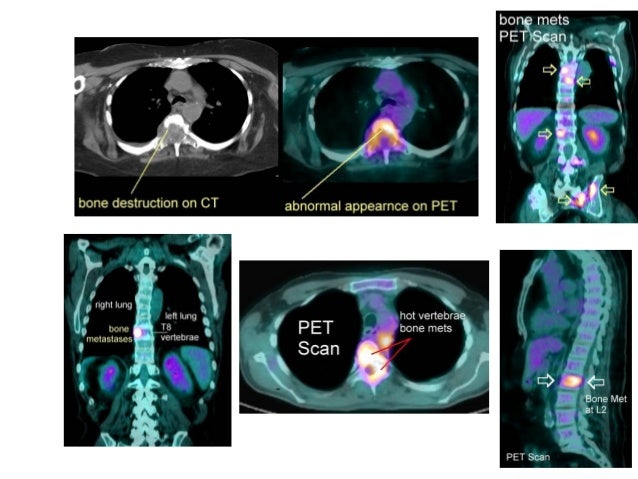

MRI

BONE SCAN

PET SCAN

19. 19. MRI BONE SCAN PET SCAN